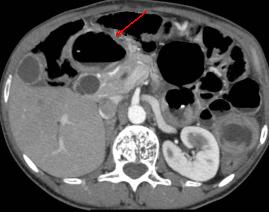

Sur la TDM en coupe axiale , c'est image

de air libre a espace superieure de l'abdomen .

Ulcere de la face anterieure duodenum perfore |

Perforation ulceres duodenale ( face

anterieure ) . Image de air libre a espace

superieure de l'abdomen . |